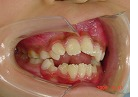

小学校高学年から治療を開始しました。

治療中ですが、治療前に比べると開咬が改善してきています。

オープンバイト治療前